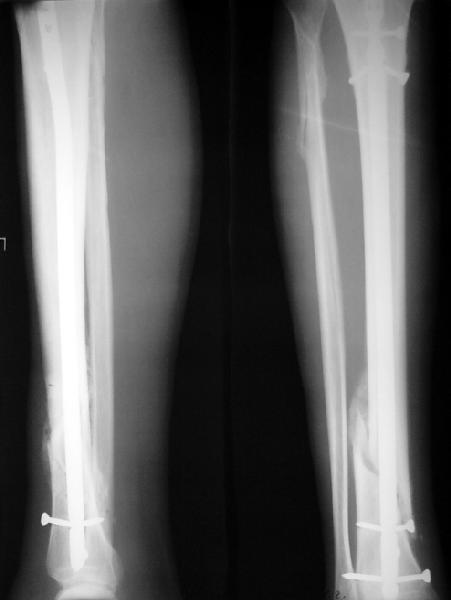

По крайней мере ходящих без дополнительной опоры через 1 месяц после операции с небольшой - при изолированной травме немало. Нестабильные по оси, кстати, не только оскольчатые, но и спиральные.

И если пациент еще не возвращается к полной нагрузке и функции, то не потому, что не разрешает врач, опасаясь несостоятельности фиксации.

Как мне показать пример? Фото стоящего на одной оперированной конечности пациента? O! Пример, подвигнувший нас на некоторое изменение технологий. Пациент этот ходил с полной нагрузкой вопреки рекомендациям. В качестве подтверждения - сломанный проксимальный статический винт к 1 мес., а к 2 мес. - все остальные. Сейчас мы перешли на более fool-proof остесинтез.

Ok. А также и следующий, в 3 месяца.

Сверху - один статический винт, а снизу - три. Что раньше сломается? Конечно, он потом и нижние сломал, и Вы правы, если бы верхний динамичесий винт уже уперся бы в нижний край отверстия, будь гвоздь подлинее, перфорировал бы сустав как пить дать.

Как я уже говорил, мы сделали выводы из этого и других подобных случаев. Очевидно, решений проблемы два - либо уменьшить нагрузку, либо увеличить прочность фиксатора. Первое решение работает не со всеми больными, так что пошли по второму пути - мы больше не используем гвозди с запирающими винтами диаметром 4 мм.